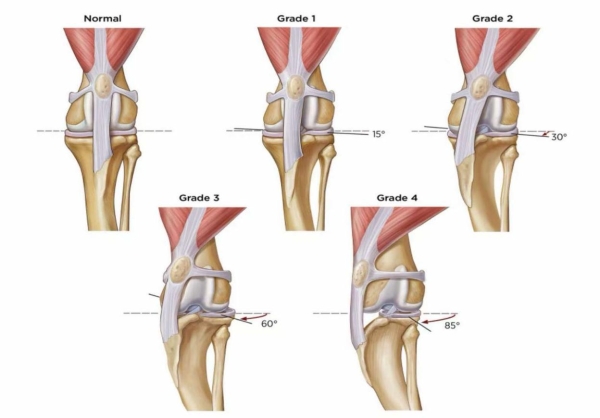

髌骨脱位是一种常见疾病,尤其在小型犬中更为多发。按严重程度分为1-4级。Coco左侧已达最严重的4级,意味着髌骨完全脱位且无法自行复位,伴随骨骼畸形和关节磨损;右侧为3级,髌骨频繁脱位但可手动复位。若不及时手术,Coco将面临关节炎加重、肌肉萎缩甚至有可能终身残疾的风险。